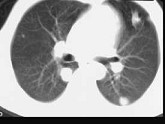

- 单项选择题男,40岁, 化脓性胆管炎手术后3天出现高热,伴胸痛, 咳嗽,CT如图, 最可能的诊断为 ( )

D、肺多发性脓肿